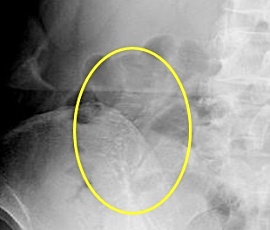

約6年前より繰り返す右側腹部痛と下痢を主訴にて精査目的に受診。腹部レントゲン検査にて、右側結腸の腸間膜側に一致した石灰化を認め、精査の結果、典型的な結腸辺縁静脈の石灰化と診断。手術(腹腔鏡下結腸切除術)を施行した。病理診断結果は、静脈硬化性大腸炎であった。

レントゲン画像